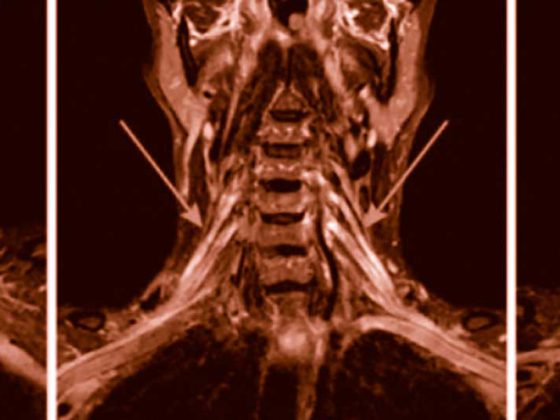

Psoriasisarthritis (PsA) betrifft bis zu ein Drittel der Psoriasispatienten und kann unterschiedliche Gelenk- und Organmanifestationen aufweisen. Dieser Beitrag vermittelt einen kompakten Überblick über klinische Präsentationen, diagnostische Herausforderungen sowie aktuelle therapeutische Strategien gemäß internationalen Leitlinien – inklusive neuer zielgerichteter Therapien. Der Fokus liegt auf Früherkennung, Differenzialdiagnose und individualisiertem Management zur Vermeidung irreversibler Gelenkschäden.